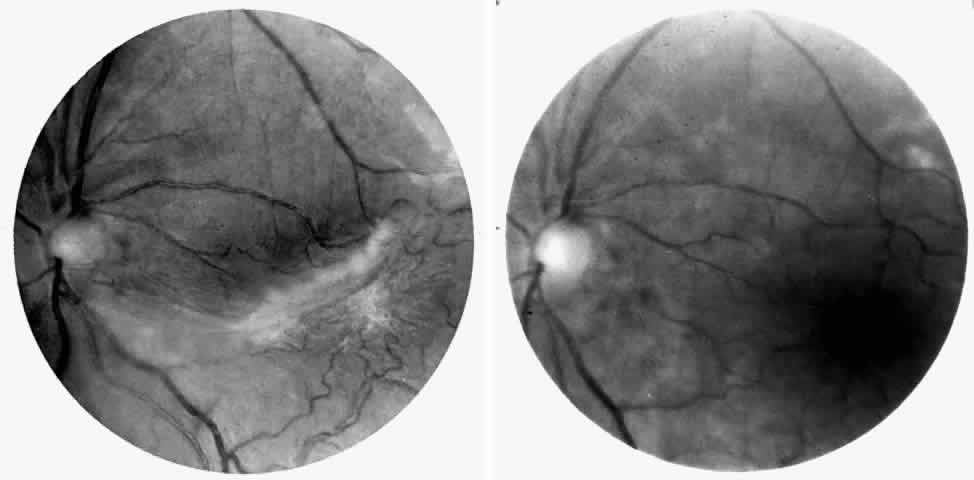

Choroidal Vascular Occlusions

Choroidal vascular occlusions may occur focally at the level of the choroidal precapillary arteriole or capillary bed (Elschnig's spots) or from posterior ciliary artery occlusion. Although focal precapillary arteriole occlusions have not been specifically identified with sickle cell disease, clinical and histopathologic evidence of spontaneous posterior ciliary artery occlusions have been reported in sickle cell disease.109,110 The findings are similar to those described following compression of the eye during general anesthesia and after heavy peripheral photocoagulation.111,112 In the acute phase, the occlusions appear as white, circumscribed, triangular patches at the level of the retinal pigment epithelium and outer retina. Over the following weeks, the white lesions fade and retinal pigment epithelial mottling develops (Fig. 15). Since patients with acute ciliary artery occlusions may be asymptomatic and the diagnosis is often based solely on the appearance of peripheral pigment mottling, the frequency of this complication remains uncertain.

Fig. 15. A 25-year-old man with homozygous sickle cell anemia and proliferative sickle retinopathy. A. Photograph demonstrating nonperfusion and wedge-shaped pigment mottling representing a choroidal infarction. B. Fluorescein angiogram demonstrating hyperfluorescence at the level of the retinal pigment epithelium.